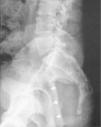

Varón de 30 años sin antecedentes de interés que acudió a nuestra consulta por una lumbalgia de un año de evolución de intensidad creciente y con mala respuesta a tratamiento con antiinflamatorios. La exploración física era anodina. La analítica completa, proteinograma y hormonas tiroideas no presentaron alteraciones relevantes. La radiografía simple de columna lumbo-sacra (fig. 1) mostró una lesión con componente predominantemente lítico en zona sacrococcígea y con evidente efecto masa a nivel presacro. Se decidió su ingreso hospitalario para completar el estudio que incluyó una resonancia magnética de pelvis (fig. 2), que confirmó una tumoración de apariencia lobulada en la zona sacrococcígea, de 14 × 9cm, asociada a una voluminosa masa de partes blandas. Se realizó una biopsia de la masa guiada por tomografía computarizada, en la que se visualizaron pequeñas calcificaciones amorfas intratumorales.